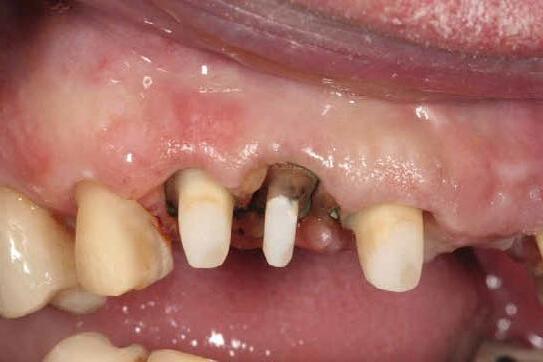

Biodentinee in Bio-Bulk

Fill Procedure

Introduction

Symptomatic teeth that are found to have cracks are one of the more difficult situations for which to plan treatment. Many articles have been published regarding these teeth and unfortunately, there has been no consensus on the best course of treatment. In my experience, it is best to treat these teeth conservatively as this allows for further treatment options if the conservative treatment fails.

Case report by Dr. M. Paul Renner

Clinical signs and symptoms

In 2018, a 59-year-old patient presented with vague pain in the upper left region. He had difficulty locating which tooth was painful, but he reported that he thought it was one of the last two teeth (tooth 26 or 27).

No teeth were tender to percussion. Tooth 26 reacted strongly to cold testing while the other teeth reacted normally. Tooth 26 tested positive to biting on damp gauze but the sensation did not linger. Both tooth 27 and 25 were negative to the bite test. The composite resin restoration in tooth 26 was removed under rubber dam and crack lines could be seen under the restoration (Fig. 1), with the most obvious running from the lingual to the centre of the tooth, and another from the mesiobuccal to the centre. A number of other minor cracks were visible, including one that ran under the buccal cusps (Fig. 1).

a core material for indirect restoration

Fig. 1

These crack lines were discussed with the patient and he was given the option of either restoring the tooth with direct composite resin or with a full- coverage indirect restoration. The patient chose to have the tooth restored with a direct composite resin and so this was performed at this appointment. The patient returned annually for examination and reported the tooth was asymptomatic.

In 2024, the patient presented again with pain in tooth 26. He reported the tooth was very sensitive to cold, with the pain lasting several minutes. He also reported that the tooth had ached spontaneously at times. On examination, the tooth reacted very strongly to cold, which lasted for almost one minute. The tooth was also slightly tender to percussion. The composite resin restoration appeared sound (Fig. 2). A PA radiograph (Fig. 3) revealed no PARL, but the pulp chamber was reduced in size when compared to a previous bite-wing radiograph.

Diagnosis

Given the tooth’s previous history of visible cracks running into the tooth and the current symptoms of moderate to severe pulpitis, a decision was made after discussion with the patient to enter the pulp chamber to assess the condition of the pulp and the depth of the cracks. The plan was to either perform a full pulpotomy or, if no viable pulp tissue was present, extirpate the pulp.

Procedure and treatment

Using local anaesthetic and rubber dam isolation, access was obtained through the composite resin restoration. While the cracks were visible, they appeared similar to the image from 2018 (Fig. 4). The roof of the pulp chamber was removed and vital tissue was found, which did not appear to be heavily inflamed (Fig. 5). A pulp stone was also present (Fig. 6). Removing this revealed bleeding pulp tissue at the opening of the root canals. A cotton pellet soaked in NaOCl was placed on the pulp tissue at the opening of the root canal and after five minutes the bleeding had ceased (Figs. 7 and 8).

As the plan was to restore the tooth with a full- coverage indirect restoration, the entire pulp cavity was filled with Biodentinee™ with the Bio-Bulk Fill technique. (Fig. 9).

The patient returned after twelve weeks and reported that the tooth had been asymptomatic (Fig. 10). At this appointment, a preparation for a ¾ crown was performed (Fig. 11). The Biodentinee™ was left in situ, cut back and used as a core for the restoration. A PVS impression was recorded, and a BISAcrylic temporary crown cemented with provisional cement (Fig. 12).

Three weeks later, a monolithic zirconia crown (Fig. 13) was bonded onto the tooth (Fig. 14). The tooth will be monitored and a review radiograph taken after six months.

Fig. 2: Pre-op composite resin restoration, 2024.

Fig. 5: Initial exposure of the pulp chamber showing slight bleeding and pulp stone.

Fig. 3: PA radiograph.

Fig. 6: Pulp stone removed.

Fig. 8: Palatal root opening with vital tissue after bleeding has stopped.

Fig. 4: Initial access showing existing cracks.

Fig. 10: Tooth at 12-week review.

Fig. 7: Buccal root openings with vital tissue after bleeding has stopped.

Fig. 9: Cavity filled with Biodentinee™.

Discussion

This case highlights a number of elements of pulpotomies in teeth with cracks. Firstly, many teeth with deep cracks have a long-standing mild pulpitis, to which the pulp has responded by producing reparative dentinee that often appears in the form of a pulp calcification. The operator must be careful when performing vital pulp therapy on these teeth as it is often difficult to differentiate the pulp calcification from the floor of the pulp chamber.

Any pulp calcifications must be removed before assessing the condition of the radicular pulp tissue.

Secondly, in teeth with pulp symptoms resulting from cracks, it is best to perform a coronal pulpotomy. This allows the floor of the pulp chamber to be examined for any extension of the crack across the floor, which would greatly reduce the prognosis for the tooth.

Conclusion

The ability to use Biodentinee™ in the Bio-Bulk Fill technique has a number of advantages in cases like the above.

The initial vital pulp therapy appointment can be shortened by completely filling the cavity and using the Biodentinee™ as a permanent dentine replacement and an interim enamel replacement. The fact that the material can be left for up to six months allows time to assess the success of the procedure before committing to the final indirect restoration. The strength of Biodentinee™ means there is no requirement to place a separate core material.